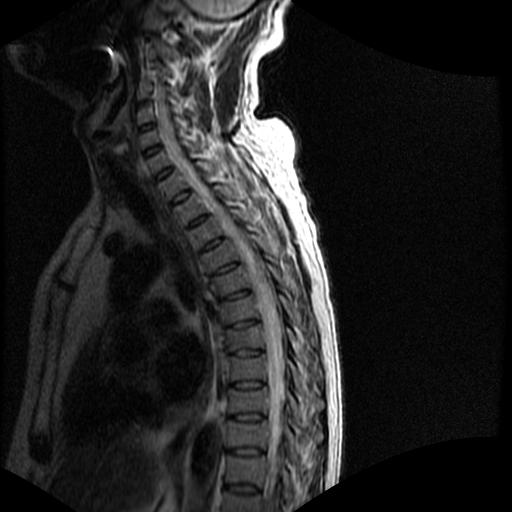

68岁男性,胸部疼痛,不适。

t7椎体前1/3信号略减低,椎体上下面凹陷,相应脊髓几周边软组织信号未见改变。考虑:椎体退变。

陈旧性压缩性骨折

胸7椎体楔状变形及信号异常,附件未见明显异常信号.椎间隙正常.未见软组织块影.考虑骨质疏松所致压缩性骨折可能大.

胸7椎体楔状变形及信号异常[t1t2 均为低信号],附件未见明显异常信号.椎间隙正常.未见软组织块影.考虑陈旧性压缩性骨折伴退变。

首先需除外单发成骨性转移瘤可能。

转移瘤也不能排除